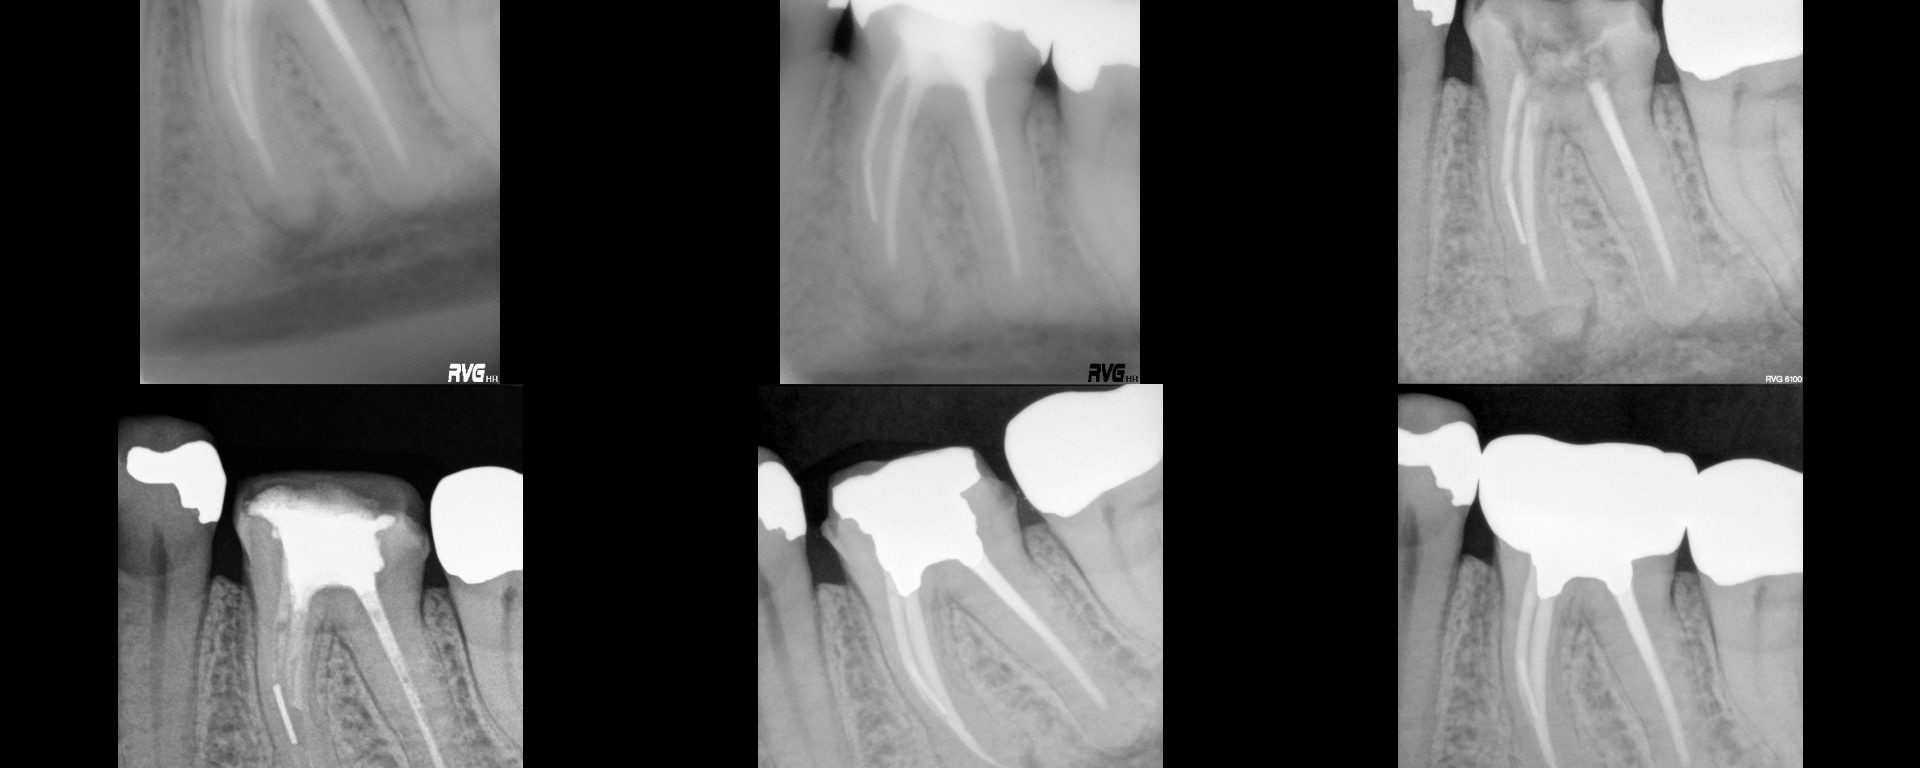

Nec/SAP. I had a historical on this from 2005…subsequent to which a Zirc was placed. I took a look at it and knew there wasn't going to be any point in a traditional access…i.e. even if I cut a traditional access, it would be a search and try-not-to-destroy in the roots.  Found four PONs. CBCT […]

My lab tech. First saw him in 2001 with the separated instrument and finding around the mesial root on this endo that "does not meet the standard of practice in contemporary endodontics."  We thought was about 20 years old at the time.  Only findings were radiographic.  Panel 2 shows a two year followup in my […]

In today regarding this tooth I treated in 2005. Stepped access, two step crown repair with amalgam internal core with HF etched, silanated, opaqued and resin veneer. Shapes were ProFile S29 #5/.06 mesials, #6/.06 distals…large for that time but I was trying it out to see if it made any difference.  Normal shapes at that […]